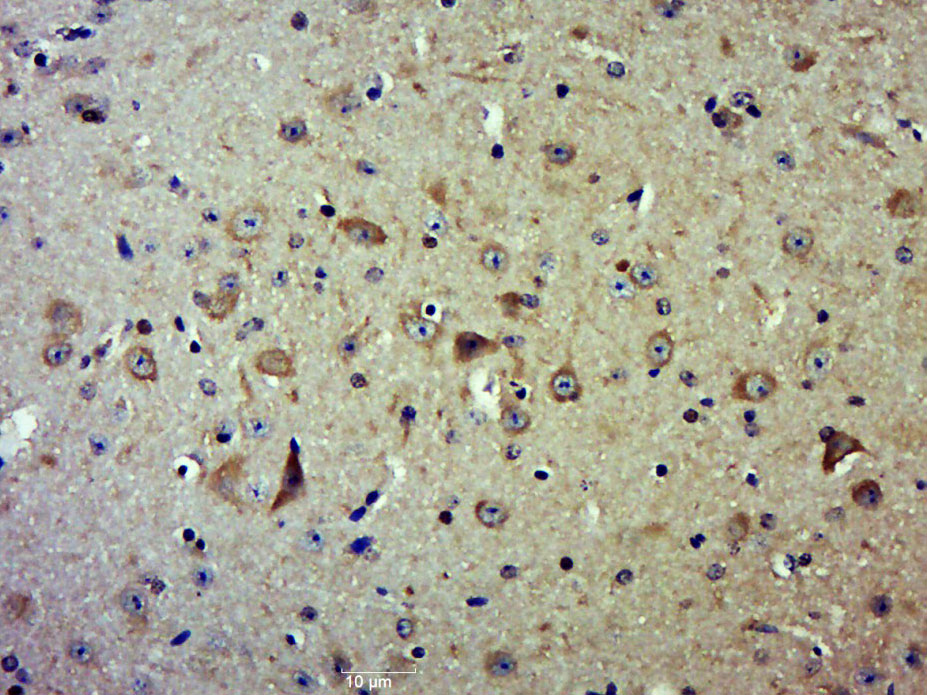

Paraformaldehyde-fixed, paraffin embedded (Mouse brain); Antigen retrieval by boiling in sodium citrate buffer (pH6.0) for 15min; Block endogenous peroxidase by 3% hydrogen peroxide for 20 minutes; Blocking buffer (normal goat serum) at 37°C for 30min; Antibody incubation with (CSK) Polyclonal Antibody, Unconjugated (bs-12941R) at 1:500 overnight at 4°C, followed by a conjugated secondary (sp-0023) for 20 minutes and DAB staining.